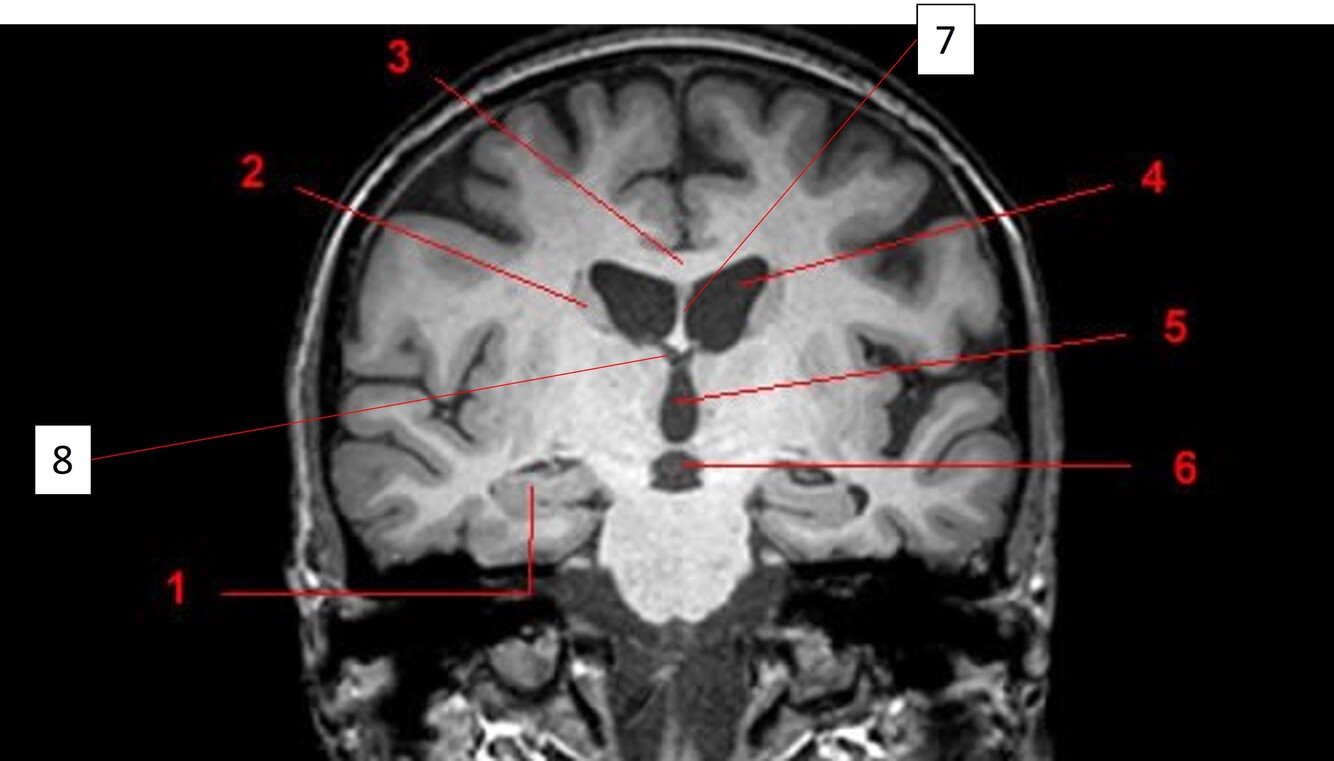

5

Q

Label 2,3,4,5,7,8

A

2=Rt Caudate nucleus

3=Corpus callosum

4=Lt lateral ventricle

5=Third ventricle

7= Septum Pellucidum

8= Rt Interventricular foramen